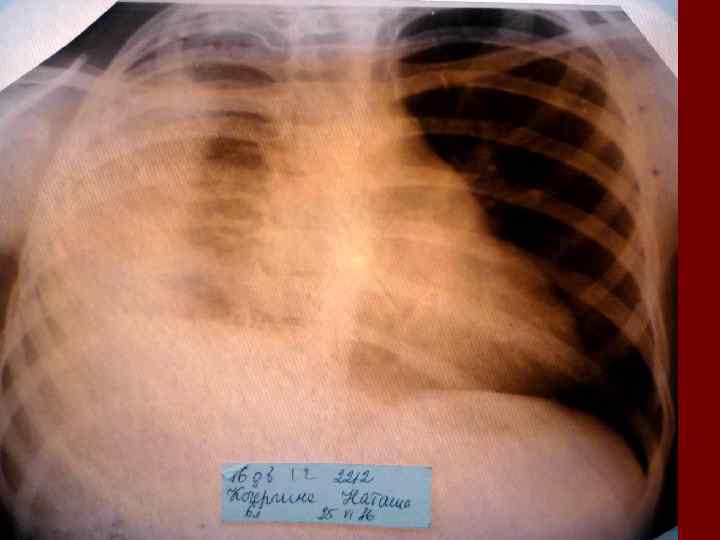

Пневмония Воспалительный процесс в респираторных отделах легкого с наличием внутриальвеолярной экссудации. n Это острое инфекционное заболевание легочной паренхимы, диагностируемое по синдрому дыхательных расстройств и/или физикальным данным при наличии очаговых или инфильтративных изменений на рентгенограмме. n Пневмония – это, прежде всего, клинический диагноз, который ставит врач у постели больного, и только затем подтверждает рентгенологически. n

Пневмония - это неспецифическое воспаление легочной ткани, в основе которого лежат инфекционный токсикоз, дыхательная недостаточность, водно – электролитные и прочие метаболические нарушение с патологическими изменениями во всех органах и системах детского организма. Заболевание диагностируется на основании синдрома дыхательных расстройств и/или физикальных данных и верифицируется рентгенологически выявлением инфильтративных изменений в легких.

Долевая пневмония характеризуется лобарным пневмоническим инфильтратом. Крупозная ( пневмококковая) пневмония диагностируется прежде всего по клиническим данным. Крупозная пневмония сохраняет свою типичную картину пневмококковой пневмонии: острое начало с характерными клиническими данными, циклическое течение, несклонность к деструкции, гомогенной и лобарной инфильтративной тенью при рентгенологическом исследовании. Вместе с тем, широкое использование антибиотиков способствовало значительному снижению числа крупозных пневмоний у детей. Интерстициальная – редкая форма пневмоний, при которой оказывается поражен прежде всего интерстиций. Как правило, интерстициальная пневмония обусловлена вирусами, пневмоцистами, внутриклеточными микроорганизмами и грибами.

Морфологическую форму пневмонии определяют по клинико – рентгенологическим данным: выделяют очаговую, очагово – сливную, долевую ( крупозную), сегментарную и интерстициальную пневмонии. Очаговая – наиболее распространенная форма. Пневмонические очаги чаще бывают размером 1 см и более. Очагово – сливная – инфильтративные изменения в нескольких сегментах или во всей доле легкого, на фоне которых могут быть видны более плотные участки инфильтрации и/или полости деструкции. Сегментарная – в процесс вовлекается весь сегмент, который, как правило, находится в состоянии гиповентиляции, ателектаза. Морфологическая картина воспаления при очаговых и сегментарных пневмониях связана с первичным инфекционным воспалением в бронхах, что дает основание отнести эти варианты поражения легочной ткани к бронхопневмониям, нередко сопровождающихся бронхообструктивным или бронхообтурационным синдромами. В настоящее время данный тип пневмоний у детей встречается наиболее часто.